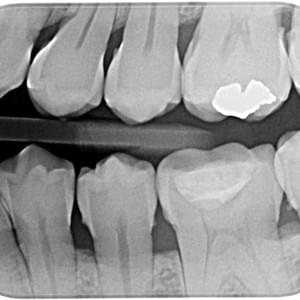

Radiografías

Periapicales, bitewing oclusales

Panorámicas, teleradiografias y CBCT con el sensor más moderno, preciso y de baja dosis.

Sirona Heliodent Plus

Colimación rectangular que disminuye en 92% la dosis necesaria, cumpliendo las mas estrictas normas europeas.